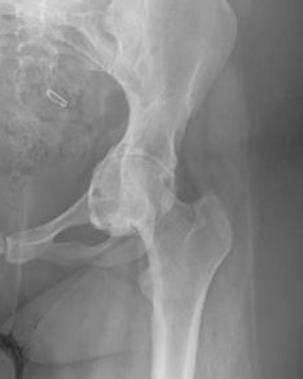

Na rycinach widoczne są:

Poniższy radiogram przedstawia:

Do charakterystycznych objawów podmiotowych lub przedmiotowych patologii widocznej na radiogramach należą: 1) dolegliwości bólowe zlokalizowane w okolicy stawu biodrowego; 2) dolegliwości bólowe zlokalizowane w okolicy stawu kolanowego; 3) gorączka; 4) objaw Drehmanna; 5) objaw Ortolaniego. Prawidłowa odpowiedź to:

Charakterystycznym objawem radiologicznym młodzieńczego złuszczenia głowy kości udowej jest: